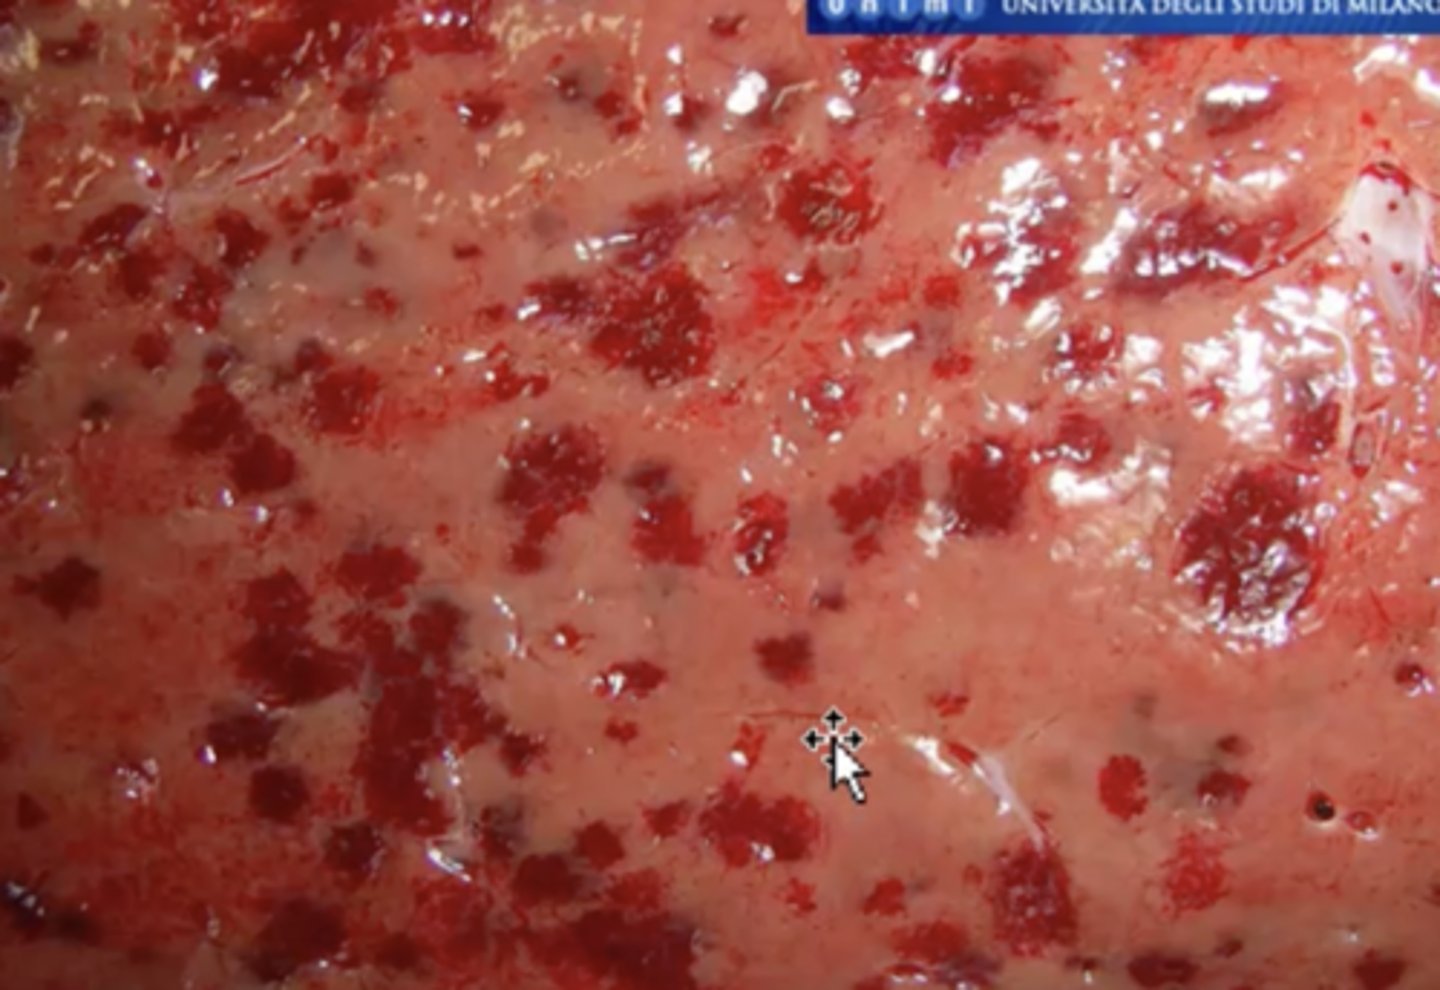

Mast cell tumor !!

-granulated

-red

What has caused this gross appearance of this liver?